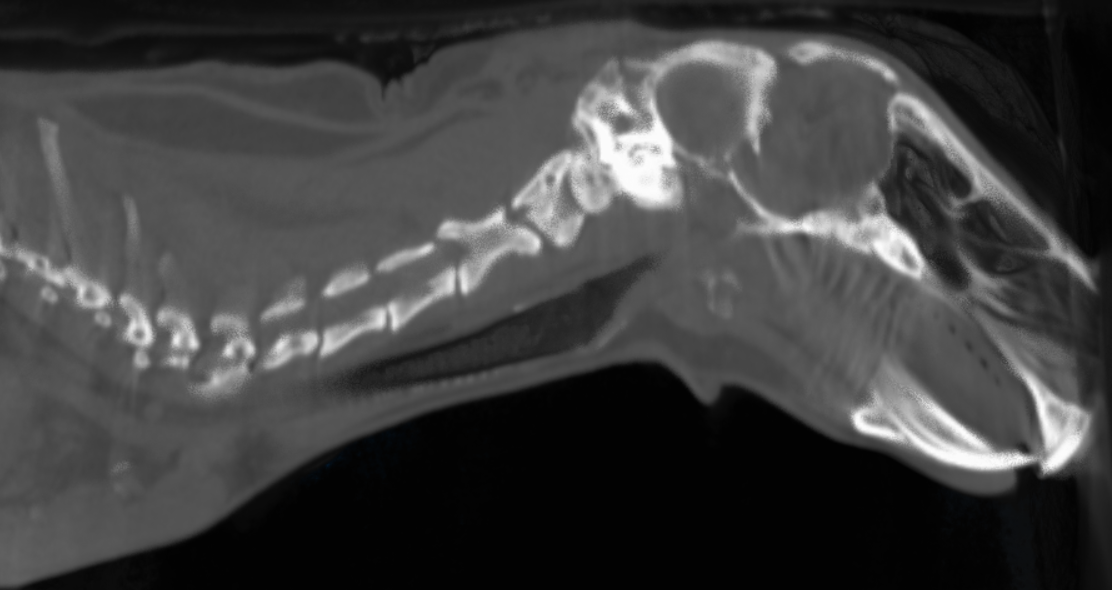

Refer to caption

Figure 5. Using our algorithm to reconstruct the volume of the RabbitCT dataset (Rohkohl et al., 2009) (512×512×5125123512512512superscript5123512\times 512\times 512\Rightarrow 512^{3}). Rendered by ImageJ 3D Viewer (Rasband et al., 1997).

4.2. Image Reconstruction Results

In Figure 5, we show an example of the generated volume data by our algorithms. The projections are from a real-world CT scanner described in the RabbitCT dataset (Rohkohl et al., 2009). Since the arithmetic computation is independent of the content of projections and volume data, we also use the volume data of RabbitCT to generate a variety of projections as described in Table 3 by a forward-projection tool in the RTK. To verify the output, we compare the reconstructed volume data with the results by RTK library, the Root Mean Square Error (Wikipedia, 2020b) threshold is less than 10e-5. Additionally, we employ the ImageJ (Rasband et al., 1997) (an image processing tool) to render each generated volume data and manually inspect them.